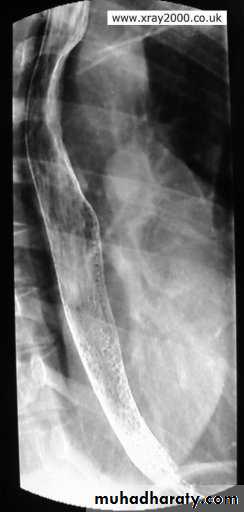

tertiary contractions

Diffuse esophageal spasm

Diffuse esophageal spasm produces intermittent contractions of the mid and distal esophageal smooth muscle, associated with chest symptoms• Congenital Anomalies